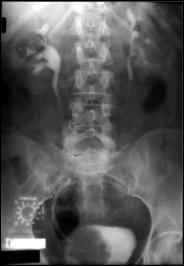

4.1. Radiografia renovezicala simpla si UIV raman examenele de baza pentru diagnosticul etiologic al oricarui pacient cu hematurie. Tumorile vezicale au drept semn radiologic cardinal imaginea lacunara pe cistograma urografica. Tumorile infiltrative pot induce modificari ale supletii peretelui vezical, care devine rigid, inextensibil, retractat etc. in zonele patologice. Ureterohidronefroza sau rinichiul mut sunt rezultatele invaziei si obstructiei ureterelor intramurale induse de tumorile solide, infiltrative (Fig.27,28,29).

Figura 28. Imagine

lacunara de 2,8/2 cm, in aria vezicii urinare, sugerand tumora

vezicala.